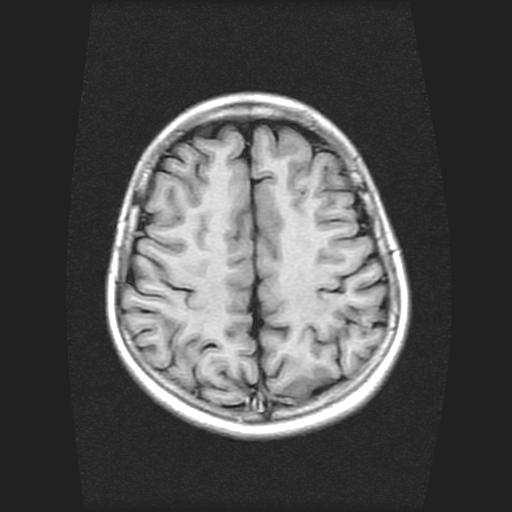

9岁女孩,三岁时诊断为癫痫,一直服丙戊酸钠,现患者一般情况良好,家长复查核磁片,看能否停药..

巨脑回

未见异常信号灶.

未发现异常信号。